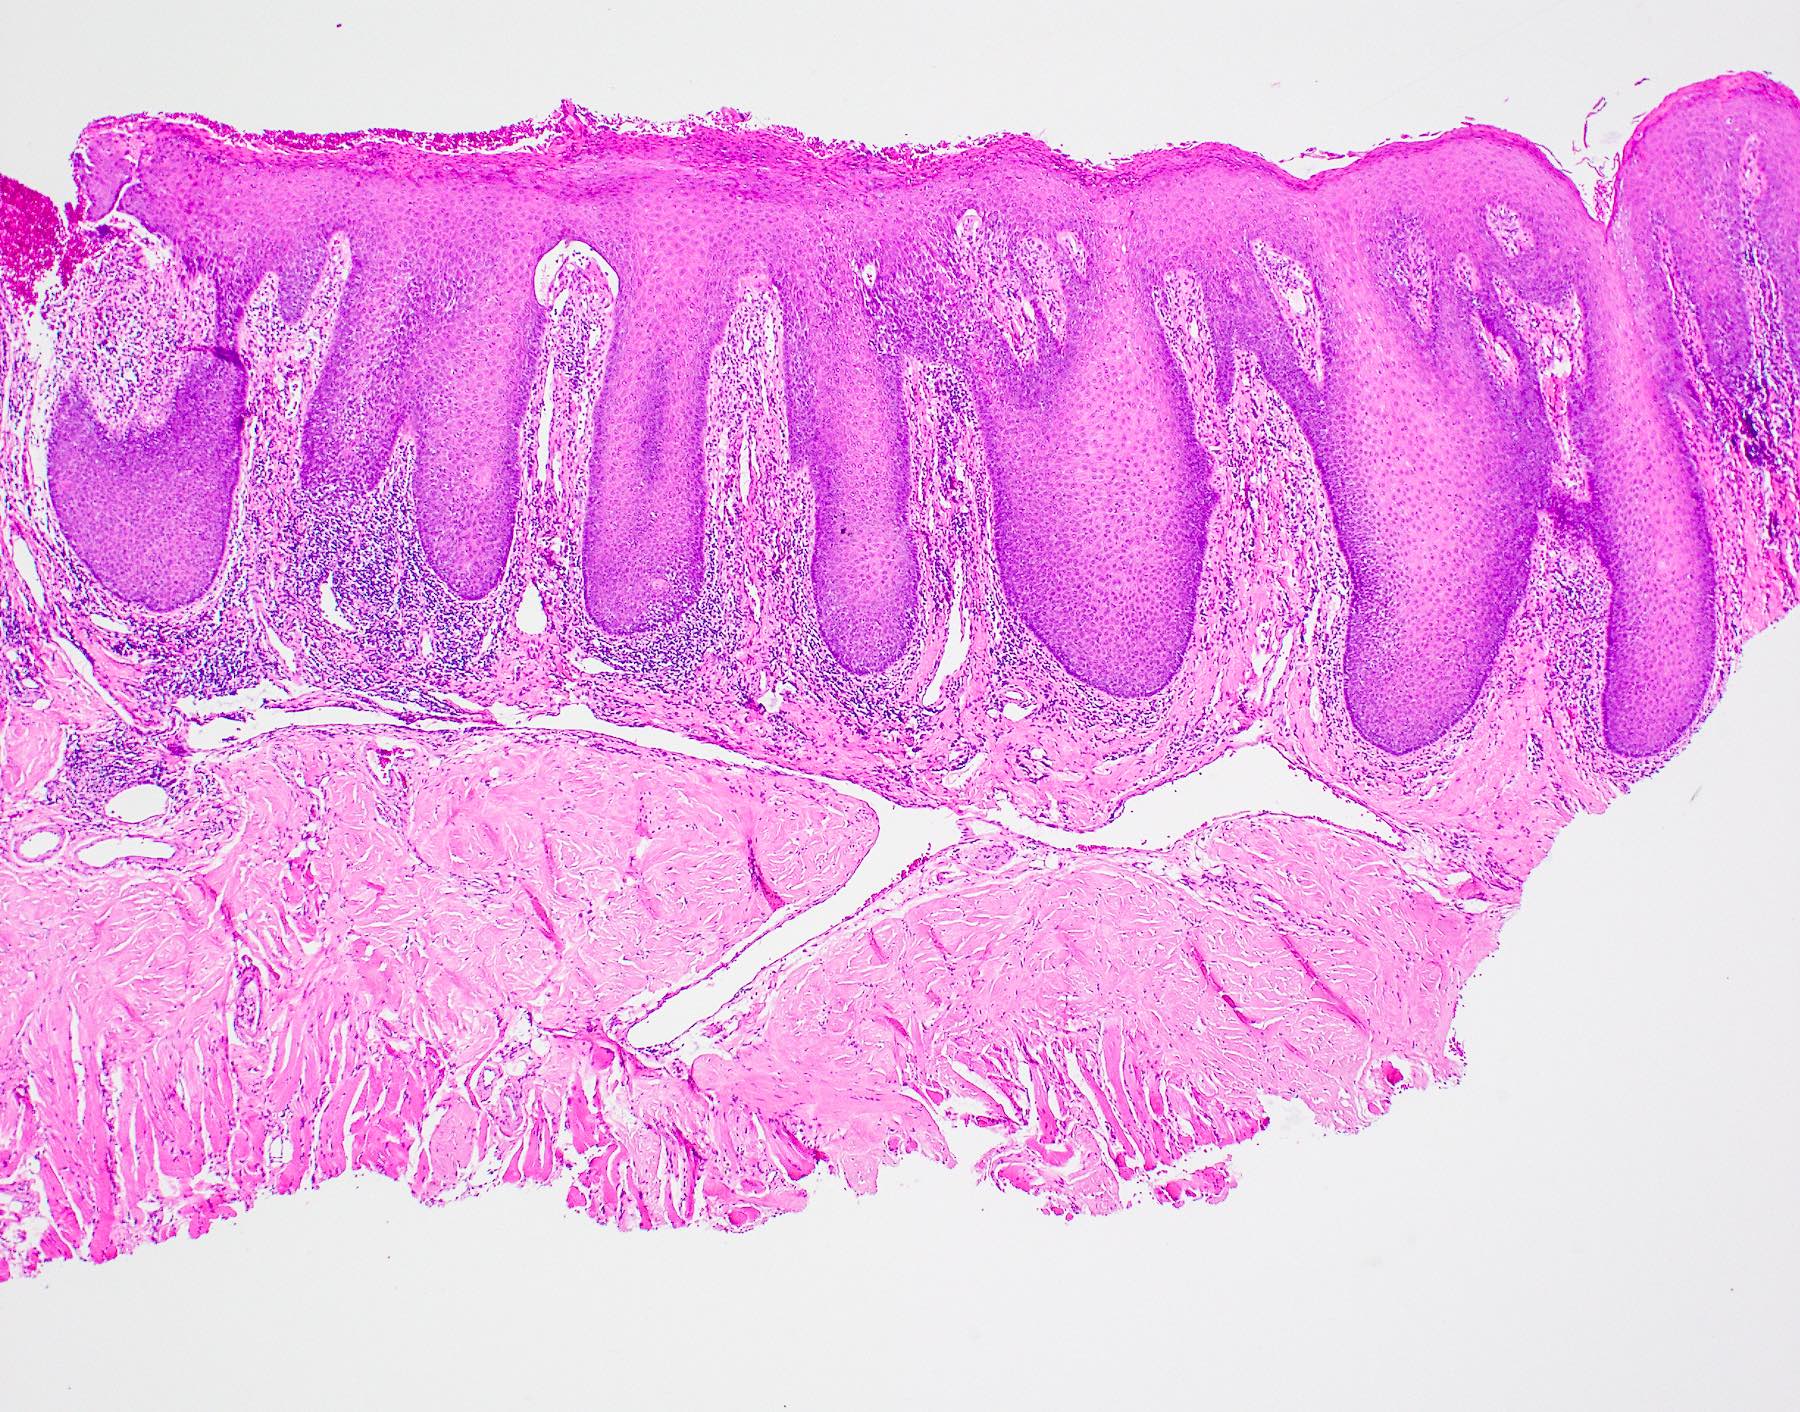

• Thick elongation of the overlying epithelium with bulbous or sometimes jagged / sharp, interconnecting rete ridges (Am J Dermatopathol 2011;33:112)

• May exhibit keratin pearl formation: concentric layers of keratinocytes with central keratinization (Am J Dermatopathol 2011;33:112)

• Lacks significant nuclear atypia; although mitotic figures may be seen, they are not numerous or atypical (Am J Dermatopathol 2011;33:112)

• Underlying stromal fibrosis may be seen in oral submucous fibrosis (in a patient who uses betel quid) or in median rhomboid glossitis, as the posterior dorsal tongue is a region that tends to exhibit prominent fibrosis of the stroma

PEH in median rhomboid glossitis

The above biopsy was taken from the posterior dorsal tongue at the midline. What is the microscopic pattern of the epithelium called?

1. Pseudoepitheliomatous hyperplasia

2. Squamous cell carcinoma

3. Squamous ductal metaplasia

4. Verrucous carcinoma

Practice answer #1

A. Pseudoepitheliomatous hyperplasia. When combined with the clinical information / photograph, the overall diagnosis of this case is median rhomboid glossitis, which is a particular diagnosis made in a patient with a red patch on the middle portion of the posterior dorsal tongue. The epithelium often shows elongated, bulbous shaped rete ridges (pseudoepitheliomatous hyperplasia) and superficial candidal colonization, as highlighted here by a PAS stain. Answer B is incorrect because the epithelium does not show significant atypia or detached islands of invasive epithelium. Answer C is incorrect because there are no salivary ducts pictured above; however, squamous ductal metaplasia may be seen in association with pseudoepitheliomatous hyperplasia in a setting of necrotizing sialometaplasia, a condition most often diagnosed on the hard palate. Answer D is incorrect because although the epithelium is bulbous and hyperplasic, a prominent verrucoid surface architecture and keratin clefting are not identified.